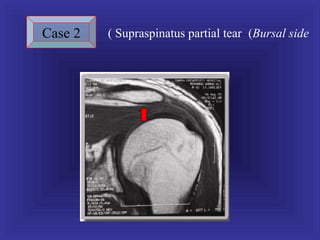

Case 2   ( Supraspinatus partial tear (Bursal side